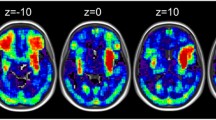

For the function-lesion mapping analysis, we first excluded patients who did not have a CT scan and those with poor quality CT scans or enlarged ventricles (N = 281). To reduce heterogeneity in our study, we also excluded patients with hemorrhagic lesions (N = 43) and left-handed patients (N = 76). Then we excluded 127 patients not assessed on the two writing tasks. Finally, as the evidence for ischemic stroke on a CT scan are unclear within the first 24 hours after stroke, we excluded those who had their scan taken on the same day of the stroke (n = 112). The analysis included a total of 267 ischemic stroke patients. (see Table 1 for demographic details of the two samples). Patients that were included in the second VBM analysis did not differ from those excluded in terms of age, gender, education year, Barthel index (all Ps > 0.05, see Supplementary Material Table 1 for details). We note that as this was an inclusive sample, the lesions cover the entire brain (see for overlap lesion maps based on the current sample: supplementary figure in Chechlacz’s paper62; Fig. 1 in Lau’s paper60), though were unevenly distributed as previously reported. For example, stroke affecting the middle cerebral artery (MCA) was much more prevalent than those affecting the anterior or posterior cerebral arteries (ACA, PCA), see details in Chechlacz’s paper63.

VBM results with raw scores (model 1 & 2) (N = 267). The VBM results overlaid on the canonical T1 images (SPM), showing lesions associated with deficits in both writing tasks (conjunction). Results of model 1 (model not included other language and motor tasks) are presented in red, and for model 2 (model included the 4 language and 3 motor tasks) in yellow. The charts represent effect size (beta) for each writing tasks and the average effect size for the language (L) and motor (M) tasks. The error bars are 90% confidence interval of the effect size. Abbreviations: L, left, R: right, SFG, superior frontal gyrus; MFG, middle frontal gyrus; IPG, inferior parietal gyrus; MOG, middle occipital gyrus; ITG, inferior temporal gyrus, IOG, inferior occipital gyrus; WW, word writing; NW, number writing; L, language, M, motor. See Supplementary Figs. 2 and 3 for case examples of lesion on the CT scans.

VBM results with PCA component (model 3, N = 267). The VBM results overlaid on the canonical T1 images (SPM), showing lesions associated with the PCA writing specific components. Lesion associated with using pen (PC 3) are presented in green, lesion associated with using pen to produce meaningful symbols (PC 4) are blue. The charts represent effect size (beta) for each writing tasks, the complex figure copy and the average effect size for the language (L) and motor (M) tasks. The error bars are 90% confidence interval of the effect size. Abbreviations: L, left, R: right, SFG, superior frontal gyrus; MFG, middle frontal gyrus; IOFG, inferior orbitalis frontal gyrus; AG, angular gyrus; MTG, middle temporal gyrus; ITG, inferior temporal gyrus, IOG, inferior occipital gyrus; WW, word writing; NW, number writing; CFC, complex figure copy; L, language tasks, M, motor tasks. See Supplementary Figs. 2 and 3 for case examples of lesion on the CT scans.